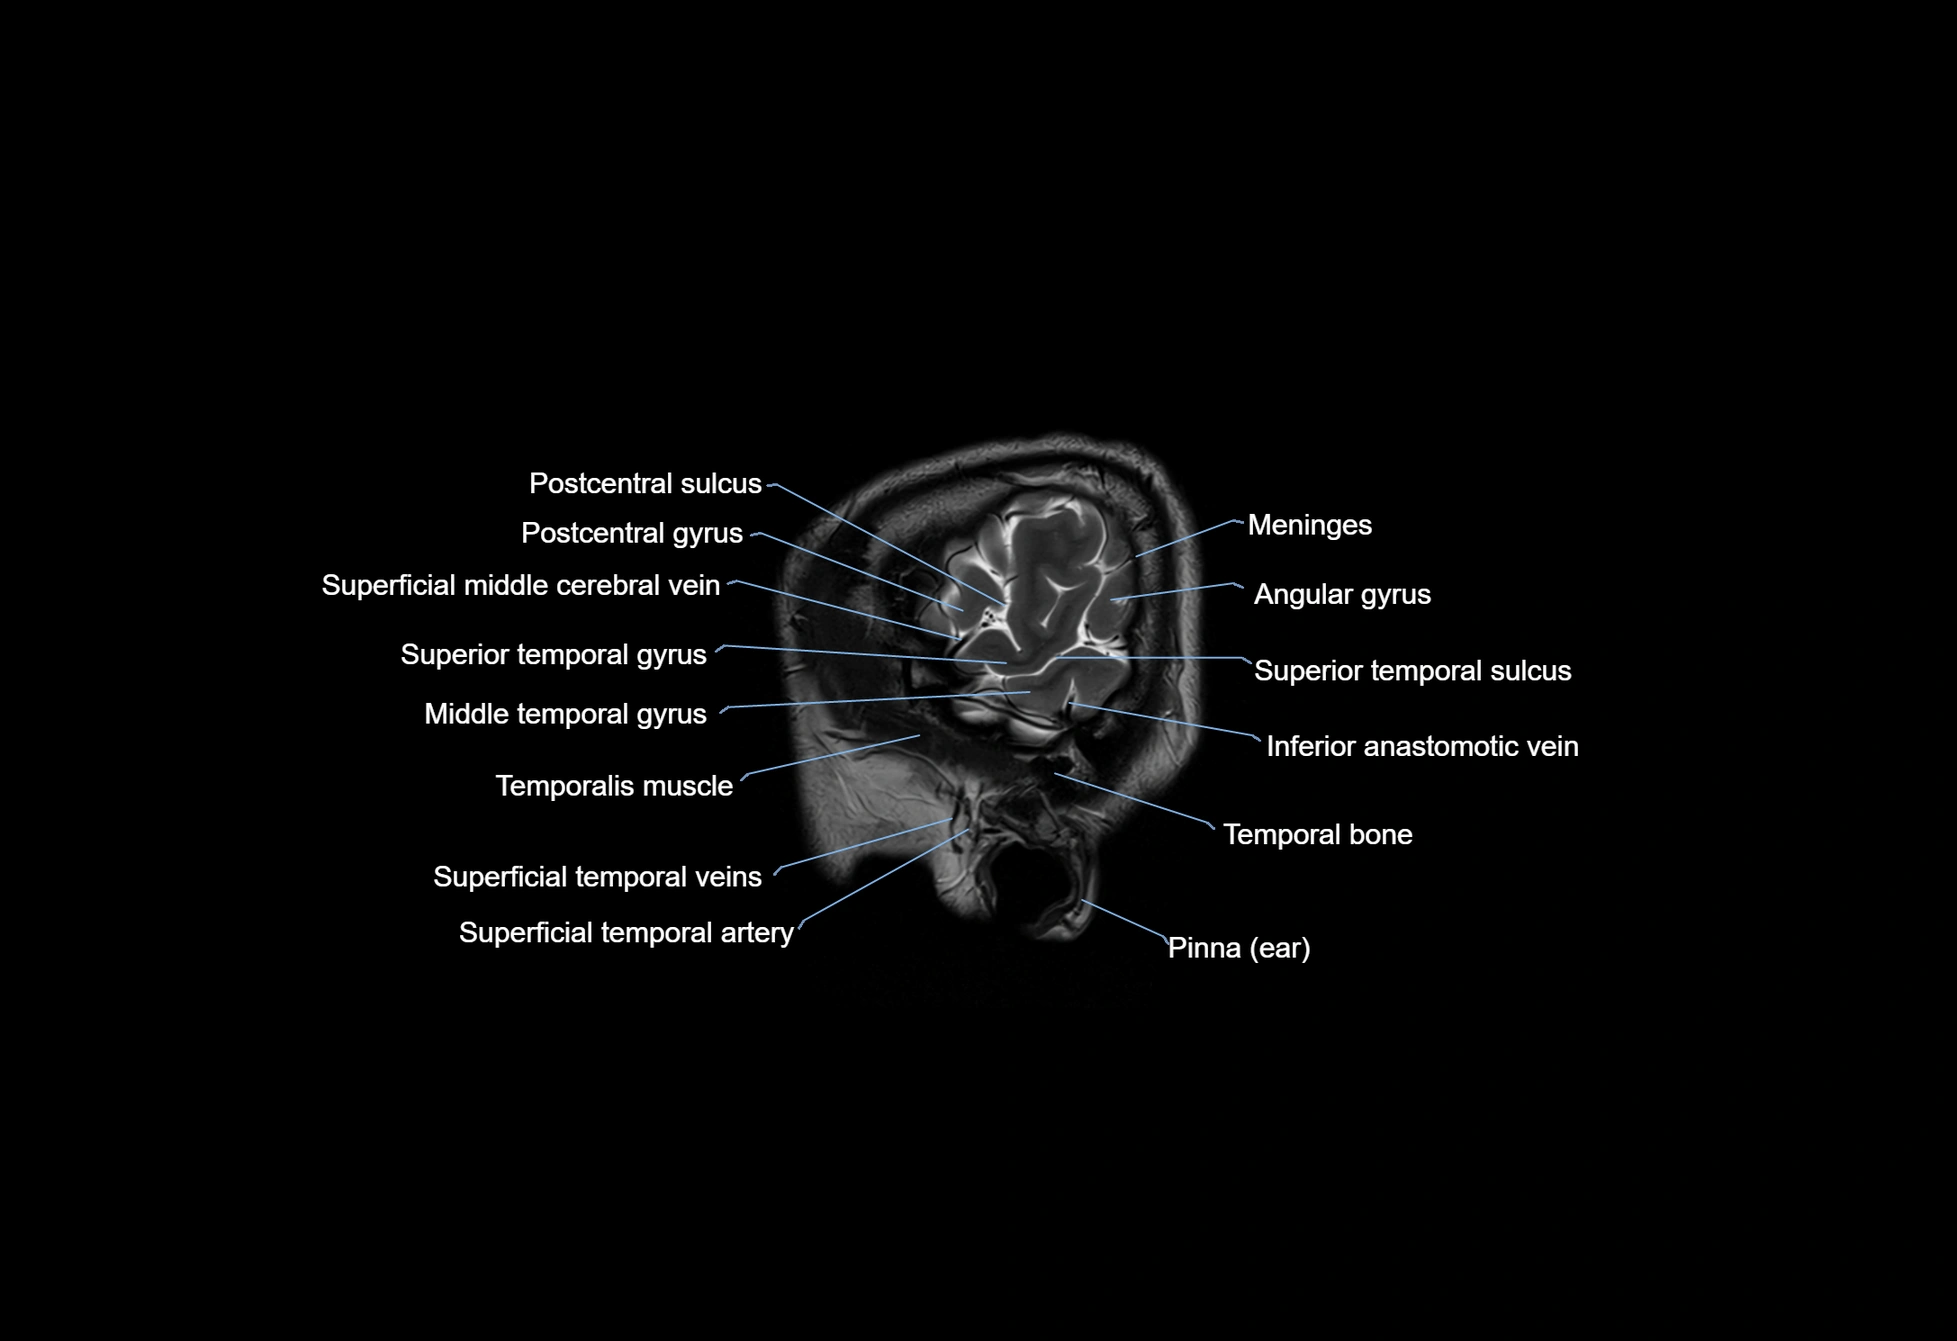

- Angular gyrus

- Inferior anastomotic vein (Vein of Labbé)

- Meninges

- Postcentral gyrus

- Postcentral sulcus

- Superficial middle cerebral vein

- Superior anastomotic vein

- Superior temporal gyrus

- Superior temporal sulcus

- Temporal bone